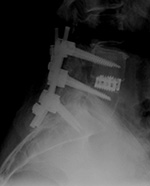

| Extensive lumbar spine fusion with pedicle screws and rods |

| A laminectomy has been performed from T12-L5. Pedicle screws and rods are at L3-S1 from the initial lower lumbar spine fusion. Later surgery added pedicle screws and rods at T12-L3, and L3-L5 with a crosslink at L2. |